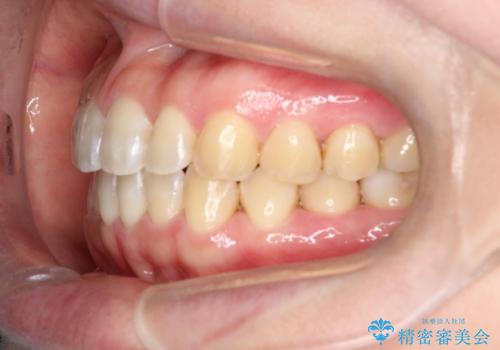

【インビザライン】前歯のすきまを閉じたい

- 前歯の隙間を主訴に来院されました。

インビザライン にて治療を行い、歯並びを改善することができました。